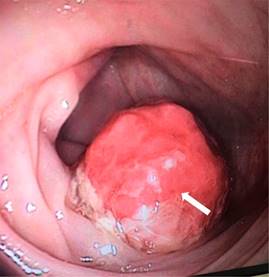

En la radiografía simple de abdomen se observó imagen de masa ocupando la luz del recto sigmoides, asociado a dilatación de colon transverso y asas de intestino delgado de manera proximal (Figura 1). Estos hallazgos se confirman en ultrasonografía abdominal, en el cual se reporta “signo de diana”, sugestivo de invaginación intestinal en abdomen izquierdo.

Figura 1: Radiografía simple de abdomen: imagen de masa de partes blandas ocupando la luz del recto sigmoides (flecha blanca) y dilatación de colon transverso y asas de intestino delgado (asterisco *).